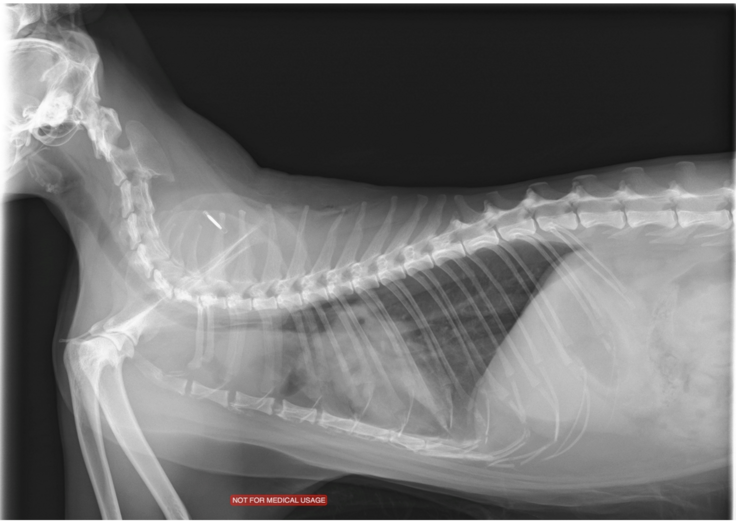

今年の1月頃から少しずつルートの元気が無くなり、体を撫でていると徐々に骨の感触が感じられれました。ルートはもともとふっくらしていたので年齢と共に瘦せてきたかなと思いましたが、やっぱり元気がないので病院で検査をすると、「胸部に水が溜まっていて早めに水を抜かないと生命に危険がある」との事でした。すぐに胸水を抜いてもらい、原因を探るために、より精密な検査が行える病院を紹介してもらいました。

獣医さんの診断でルートがリンパ腫、いわゆる”がん”である事を伝えられ状態はステージ3で、余命は1~3ヶ月であると告げられました。

↓超音波・X線検査

リンパ

腫は血液のがんで、外科的治療(摘出)ができないので以下の選択をすることになりました。